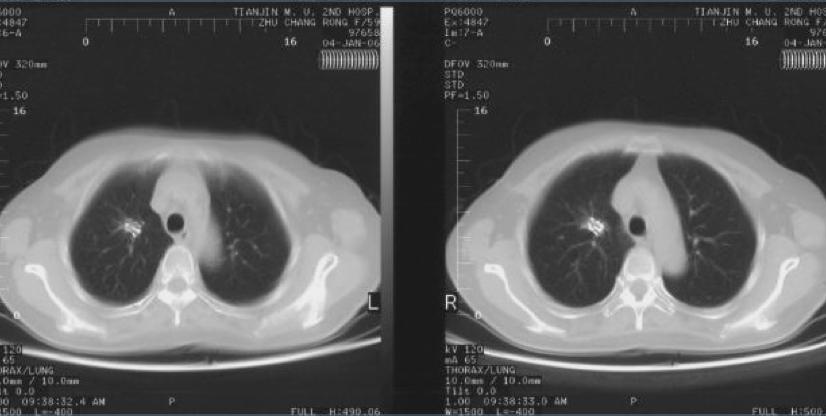

碘125粒子源植入治疗右肺周围性肺癌

术前

术后6个月疗效达到完全缓解